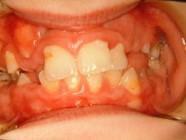

028 Δεύτερη περίπτωση Αρχική κατάσταση Η σημασία της στοματικής υγιεινής και ορθοδοντικής πρόληψης

Μετά το πέρας της ορθοδοντικής θεραπείας.